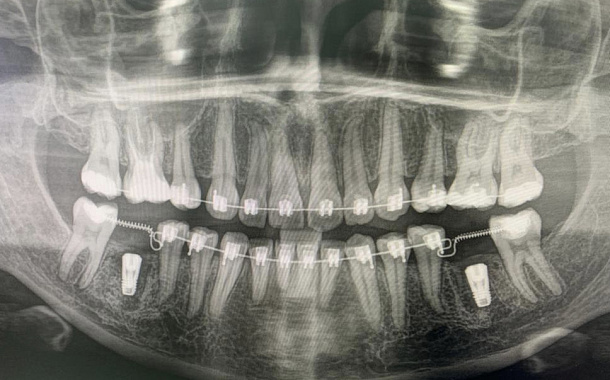

Применение Indiba после стоматологических процедур, таких как удаление зубов, костная пластика и имплантация, обеспечивает ряд значительных преимуществ:

- Улучшение приживаемости имплантатов: усиление кровоснабжения в области имплантации способствует лучшей интеграции имплантата с костной тканью.

- Исследование, опубликованное в Journal of Clinical Medicine (2020), показало, что применение Indiba после имплантации зубов ускоряет процесс остеоинтеграции на 30-40%.